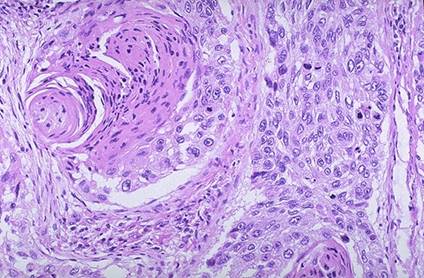

Microscopic: aspect de carcinom scuamos spinocelular, in care se observa o zona de mai slaba diferentiere in dreapta imaginii de mai jos, iar in stanga sus o perla keratozica: